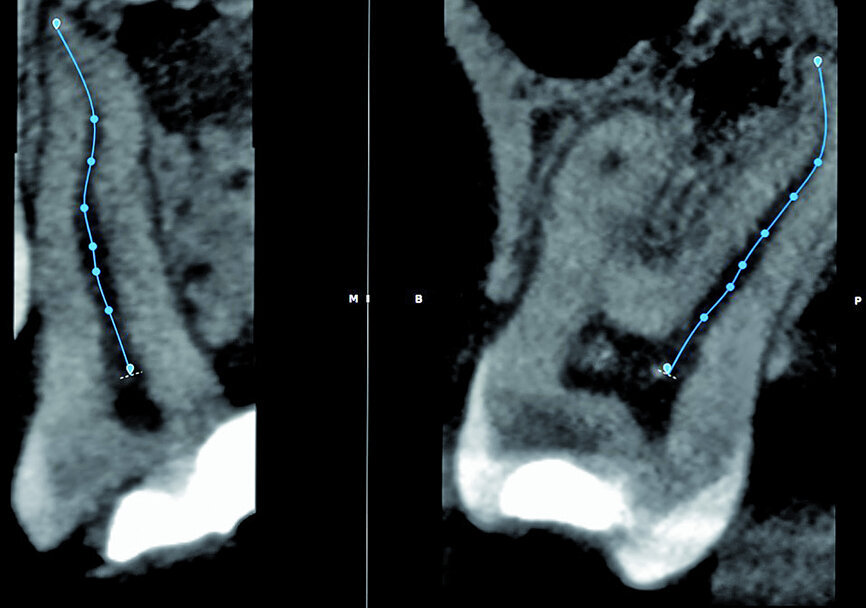

Fig. 7: The 3D Endo Software proposal of the canal anatomy that can be corrected by the operator, according to the canal configuration viewed in different planes in the software. In most cases, the proposal is very good but in this case it was not accurate because of the multi-planar canal anatomy.

Fig. 8: Corrections made for the palatal root canal according to the canal configuration that can be viewed in different planes in the software.

Fig. 9: Corrections made for the mesiobuccal root canal according to the canal configuration that can be viewed in different planes in the software.

Fig. 10: Corrections made for the distobuccal root canal according to the canal configuration that can be viewed in different planes in the software.

With the fourth step, ‘3D Canal Anatomy’, the software made a proposal of the canal anatomy (Fig. 7), but the operator can make corrections according to the canal configuration that can be viewed in different planes in the software. Figures 8 to 10 show the mapping of the palatal, mesiobuccal, and distobuccal root canal systems.